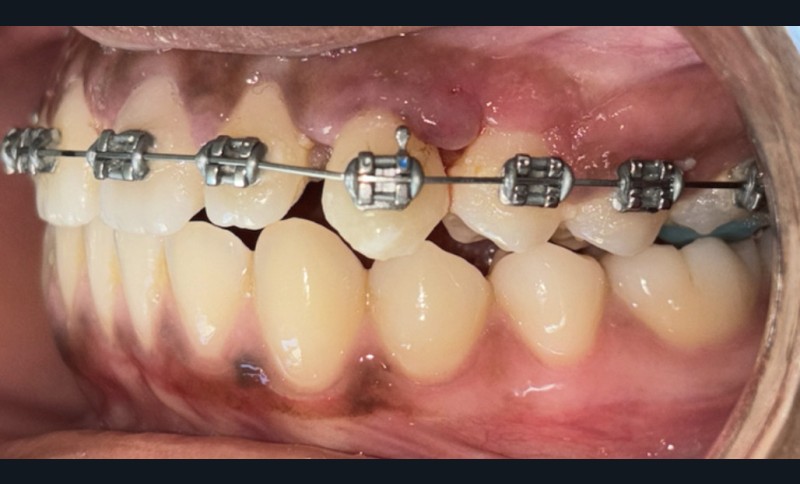

Diagnostic (fig. 1 et 2)

À l’examen intra-oral, les arcades sont paraboliques, la courbe de Spee est normale. On remarque l’absence de la 23 sur l’arcade ainsi que la persistance de la 63. La patiente présente une Classe II partielle molaire et canine subdivision droite, ainsi qu’une insuffisance de recouvrement. Un léger encombrement incisif mandibulaire est présent, ainsi que des diastèmes maxillaires avec une dysmorphie dento-dentaire de 12 et 22.

Correction de la denture

Le traitement orthodontique a été réalisé en technique vestibulaire multi-attaches 0,022’’ x 0,028’’. Après l’alignement et le nivellement de l’arcade maxillaire (arcs Niti 0,014‘’,0,018‘’, 0,017 x 0,025’’), un acier 0,019 x 0,025’’ a été mis en place. Un ressort Niti actif a permis de créer l’espace nécessaire pour accueillir la 23 sur l’arcade (fig. 3). L’espace nécessaire a été évalué par mesure de la réplique dentaire tridimensionnelle.